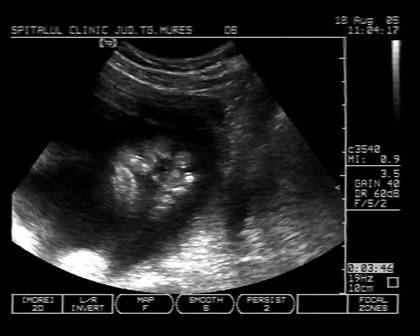

Fig. nr.251 Ciclopia din imaginea precedenta ,cu defect de inchidere pe linia mediana a fetei